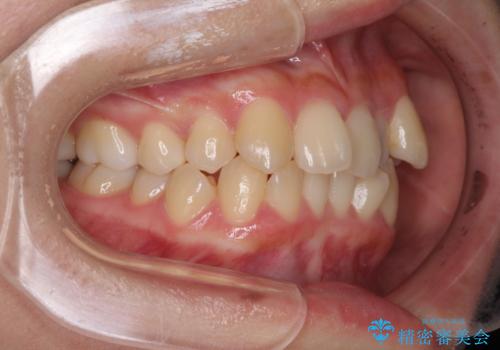

八重歯の抜歯矯正 補助装置を用いたインビザライン矯正

- 上顎の重なっている前歯を気にして来院された患者様です。

重なっている部分は抜歯が必要で、歯の移動量が多く、更には右側にずれている正中を改善する必要がありました。

インビザライン単体での治療は困難と判断し、補助装置により八重歯移動後にインビザラインを用いることとしました。

非常にしっかりとマウスピースを装着してくださいましたが、前歯の排列がなかなか仕上がらずに期間がかかってしまいました。